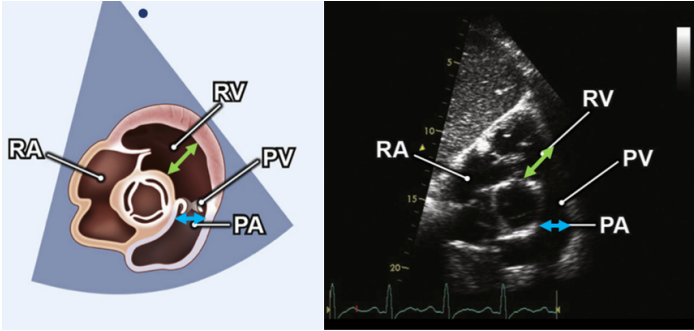

在右室流出道切面(subcostal short-axis RVOT)切面,我们可以测量右室流出道(RVOT)的内径和肺动脉(PA)内径。操作示意图见图4。

图片

图4. Subcostal short-axis RVOT切面下测量右室流出道(RVOT)的内径(绿色)和肺动脉(PA)内径(蓝色)的示意图